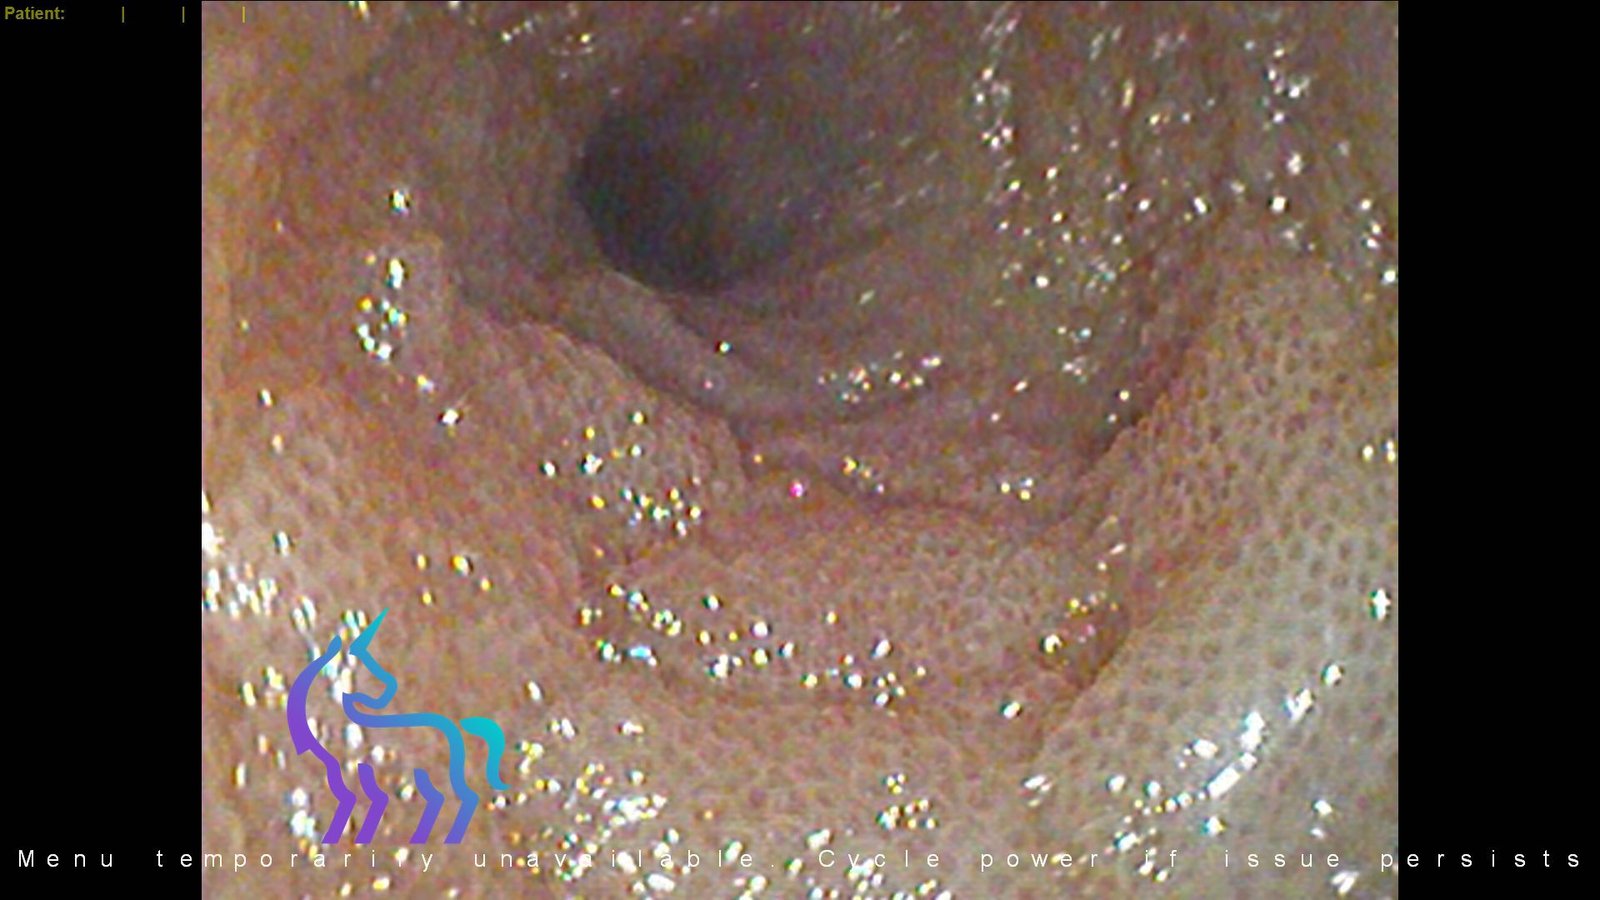

Endoscopie urinaire : Lithiases de xanthine sous Allopurinol

Espèce : ChienCe cas présente une endoscopie urinaire réalisée chez un chien suivi pour leishmaniose et traité par allopurinol. L’examen a permis la mise en évidence de calculs urinaires de xanthine.

Il s’agit d’une complication iatrogène bien décrite de ce traitement, où l’inhibition de la xanthine oxydase favorise la formation de ces cristaux spécifiques.

Diagnostic retenu : Ce cas illustre l’apport de l’endoscopie urinaire dans le diagnostic précis des lithiases et l’adaptation de la prise en charge thérapeutique.